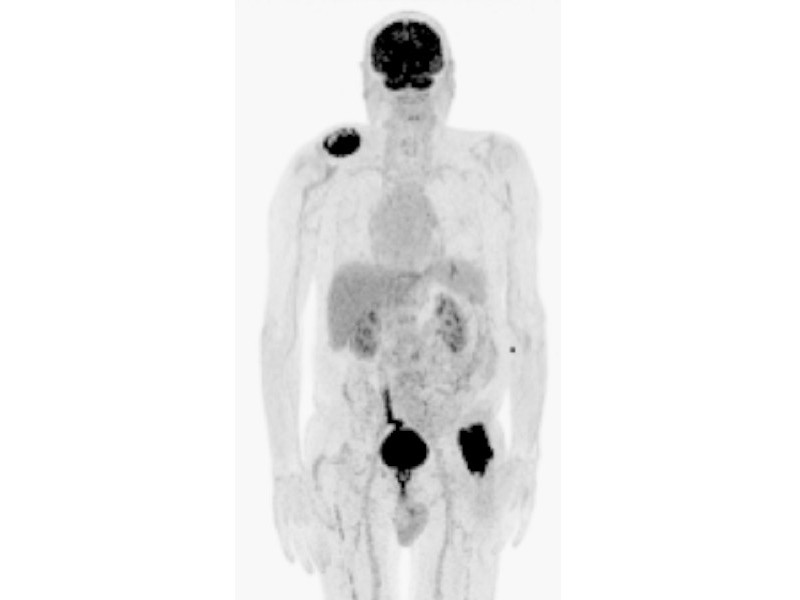

In der Nuklearmedizin spielt die Dosimetrie eine entscheidende Rolle bei der Bestimmung und Überwachung der Strahlendosis, die Patienten bei diagnostischen oder therapeutischen nuklearmedizinischen Verfahren ausgesetzt sind. Die Dosimetrie befasst sich mit der Messung, Berechnung und Bewertung von Strahlendosen, um sicherzustellen, dass sie auf ein akzeptables Maß begrenzt sind und gleichzeitig die Wirksamkeit der Behandlung gewährleistet ist.

Ein wichtiger Aspekt der Dosimetrie in der Nuklearmedizin ist die individuelle Anpassung der Strahlendosis an jeden Patienten. Dies ermöglicht es, die optimale Menge an radioaktiven Substanzen zu verabreichen, um eine präzise Diagnose oder Therapie zu gewährleisten, während das Risiko von Nebenwirkungen minimiert wird.

Die kontinuierliche Weiterentwicklung von Dosimetrietechniken und -verfahren trägt dazu bei, die Sicherheit und Effizienz nuklearmedizinischer Verfahren weiter zu verbessern. Durch präzise Dosimetriemessungen können Ärzte fundierte Entscheidungen treffen und eine personalisierte Behandlung für jeden Patienten sicherstellen.